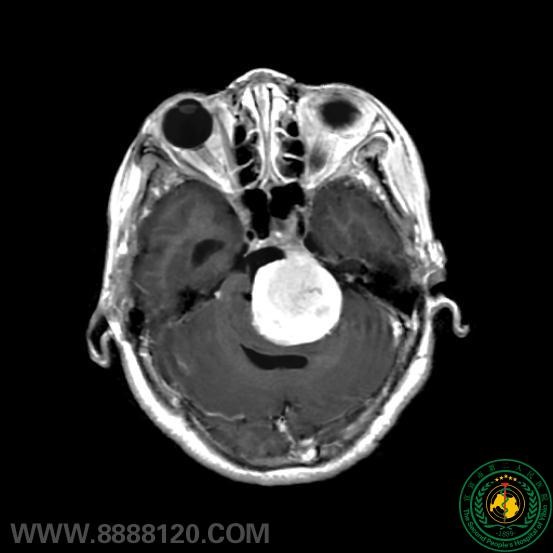

苦战7小时,宜宾市第二人民医院神外一科顺利成功切除后颅窝巨大肿瘤

苦战7小时,宜宾市第二人民医院神外一科顺利成功切除后颅窝巨大肿瘤40189